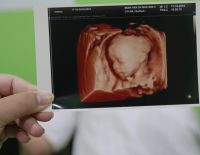

Siêu âm màu là gì? Lợi ích và thời điểm thực hiện siêu âm màu

Siêu âm màu trong thai kỳ giúp cha mẹ lưu giữ được hình ảnh của con từ khi còn trong bụng mẹ để làm kỉ niệm. Ngoài ra còn rất nhiều lợi ích mà siêu âm màu mang lại. Cùng giải đáp những thắc mắc...